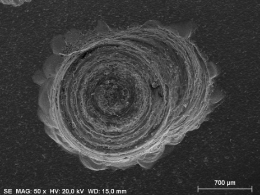

Preparo com CVDentus: Sem danos à membrana pulpo-dentinária. Preservação dos odontoblastos (CO), dentida tubular (DT), pré-dentina (PD) e zona acelular (ZA).